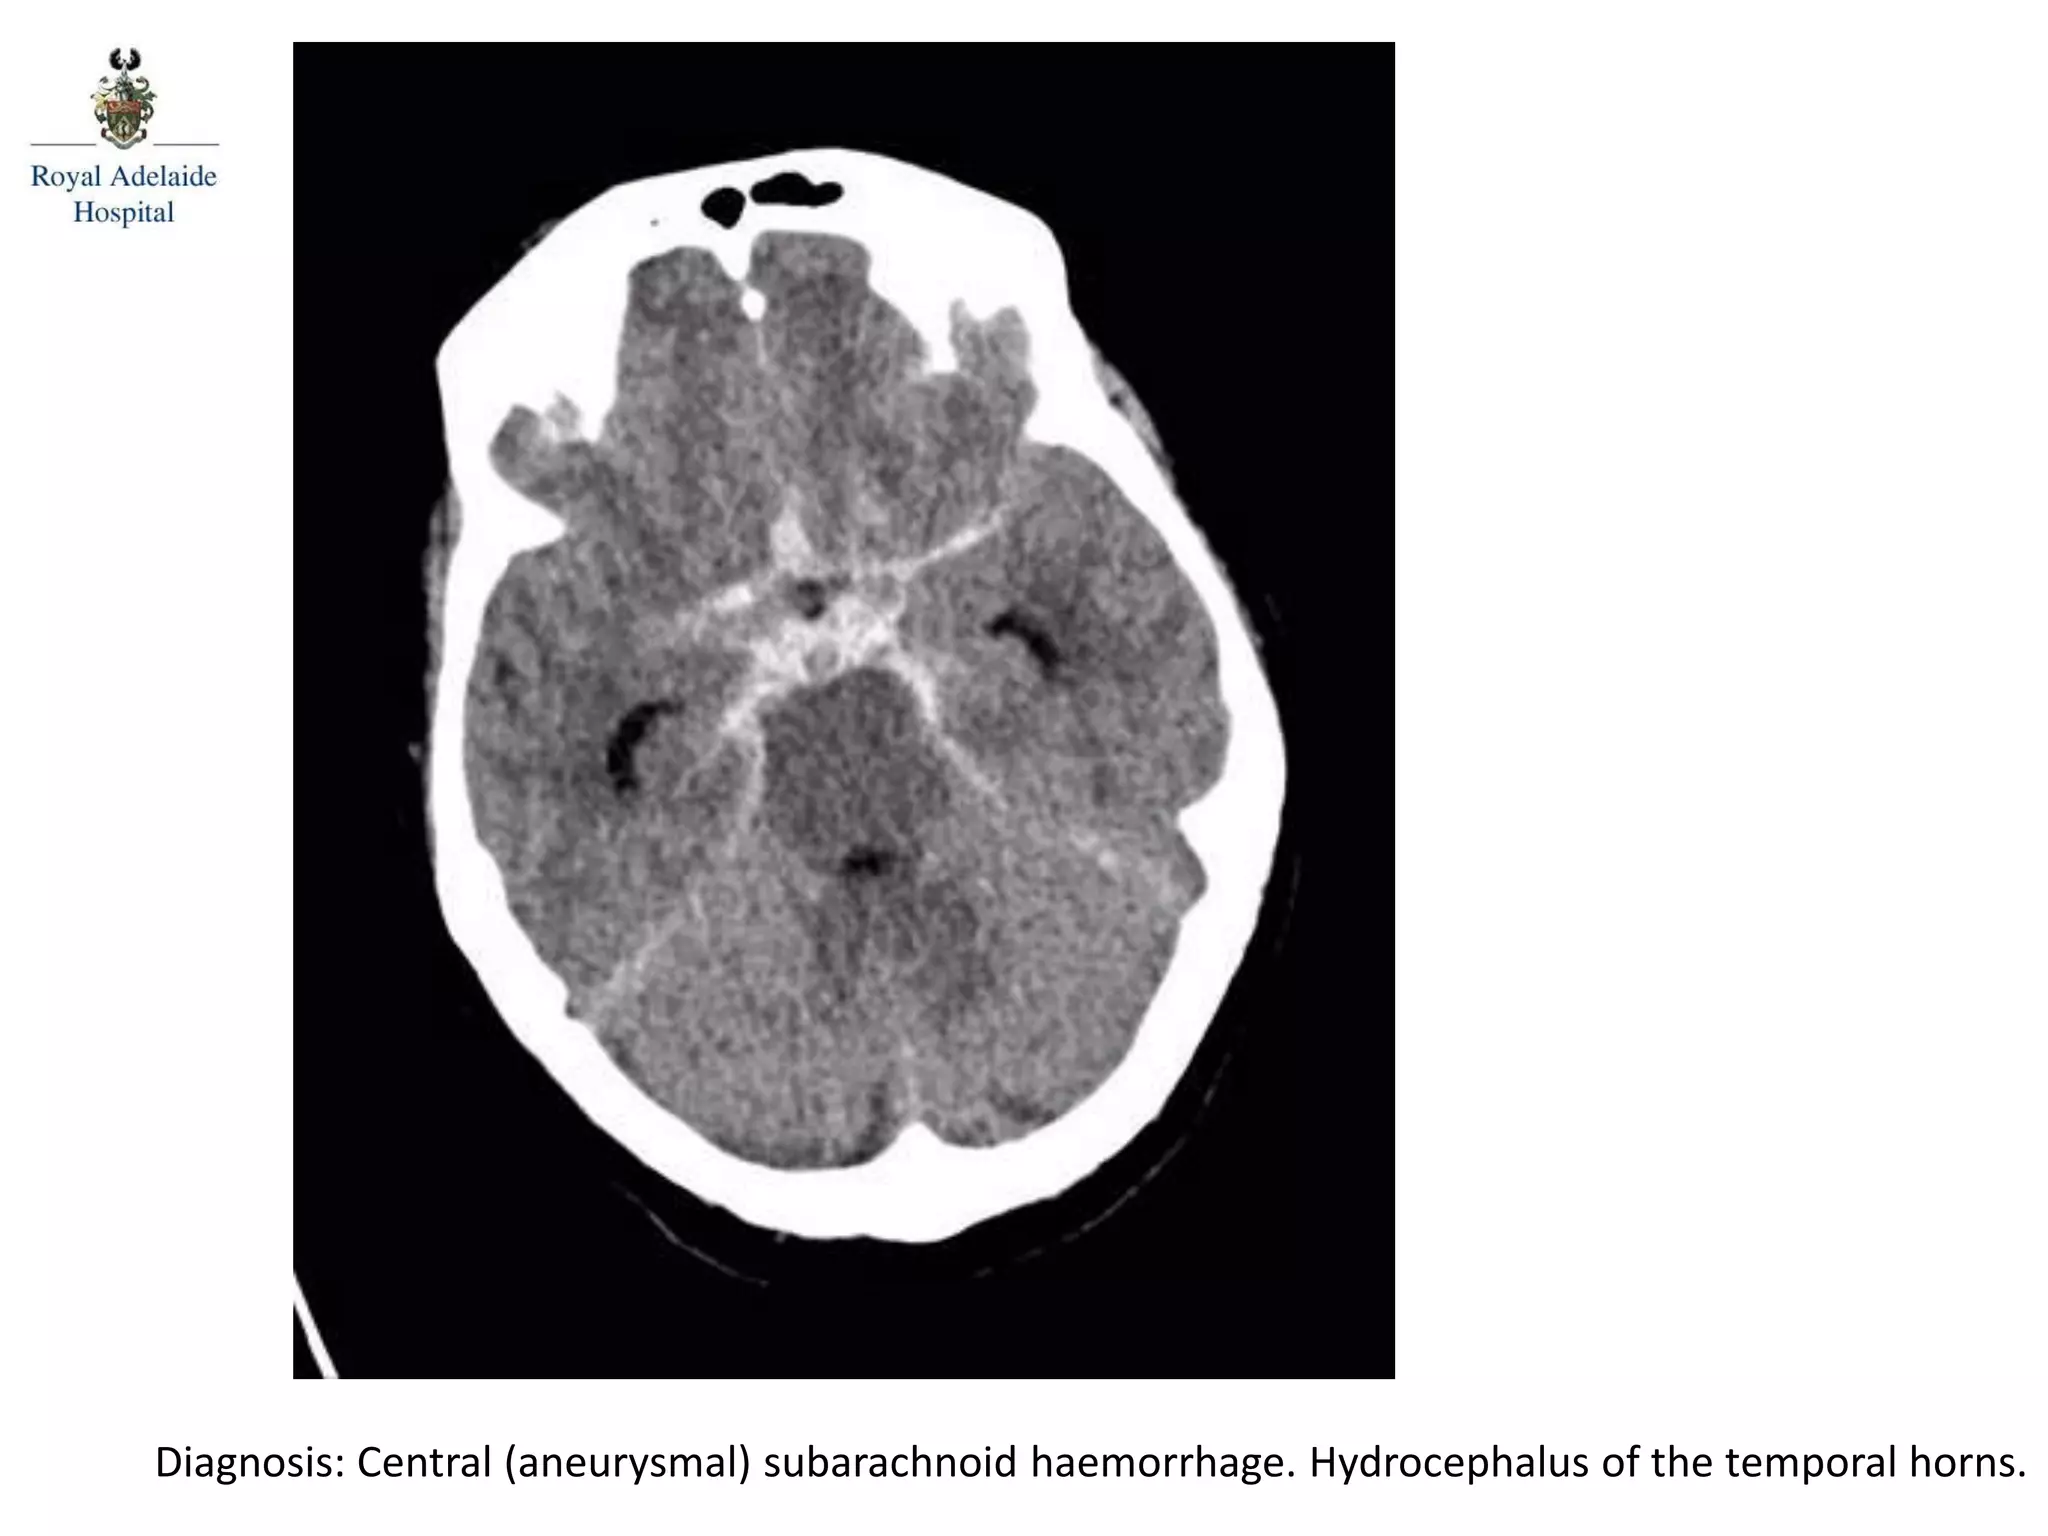

The document outlines multiple diagnoses from head CT cases, including small left basal ganglia bleed likely due to hypertension, various types of subdural and subarachnoid hemorrhages, and evidence of hydrocephalus. It details traumatic origins of some hemorrhages and notes obstructing masses and atrophic changes. Overall, there are significant findings indicating complications related to cerebral hemorrhages and ventricular enlargement.